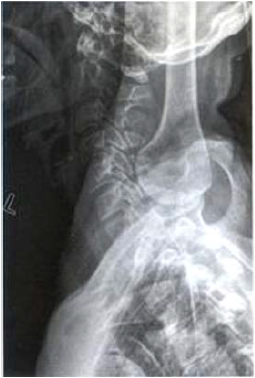

A figura abaixo é um exame radiográfico que corresponde a que posicionamento?